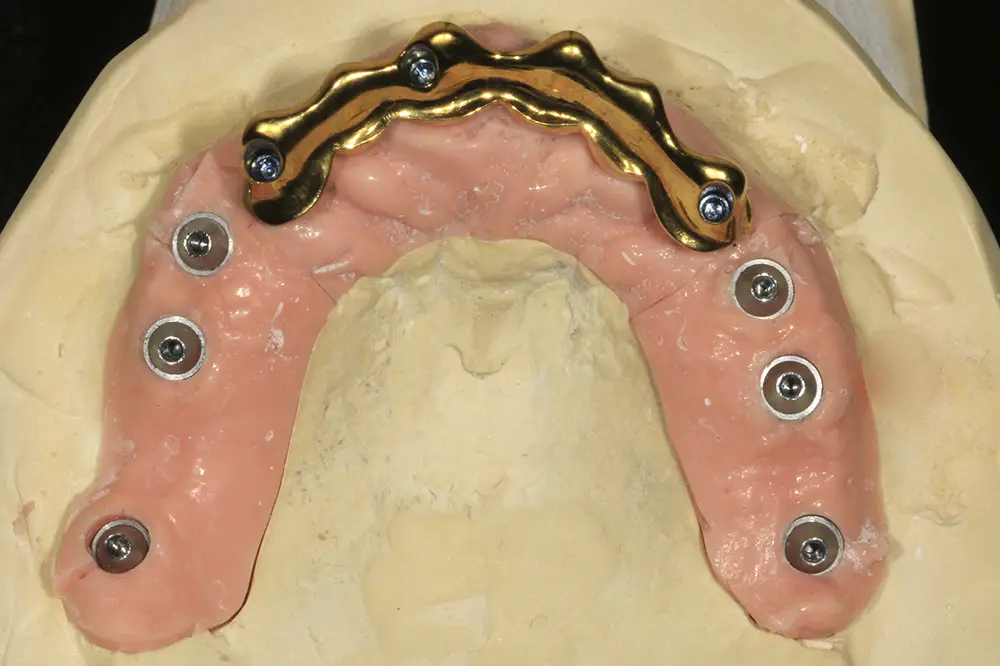

Transcurridos cuatro meses desde la fase inicial, ya tenemos suficiente hueso disponible en las zonas donde se realizaron las extracciones y regeneraciones con PRGF-Endoret, por lo que podemos planificar la colocación de implantes en estas áreas en un segundo tiempo quirúrgico. En el primer cuadrante, en los cortes del cone-beam realizado en este momento podemos observar una regeneración completa del alveolo tanto del molar como del premolar extraídos en la primera fase y cómo podemos colocar implantes, cortos y estrechos también en estas localizaciones (figs. 27-28). En esta fase, se aprovecha además para extraer los dos caninos que han cumplido con su función de permanecer durante la fase inicial de provisionales y cargar ya los implantes superiores de la primera fase con una prótesis atornillada mediante transepitelial múltiple y una estructura de barras articuladas, que permitirá de forma sencilla posteriormente ir añadiendo aquellos implantes que quieran cargarse seguidamente sin necesidad de repetir la estructura completa (figs. 29-31).

Figs. 29-30. Imágenes de la prótesis de carga progresiva, ya apoyada sobre los implantes superiores.

Transcurridos de nuevo cuatro meses más desde la última cirugía, se confecciona una prótesis de carga progresiva que engloba todos los implantes. El implante situado en la posición 22, colocado en la primera fase quirúrgica, es explantado en este momento, tratado por lo tanto como implante transicional que permitió la carga progresiva en los primeros momentos, siendo prescindible actualmente desde el punto de vista biomecánico para una mejor confección de la prótesis final (fig. 38). Esta carga se mantiene durante 2 meses más, momento en el cual se comienza la confección de la prótesis definitiva. Para ello, se realiza como primer paso el encerado diagnóstico, que se prueba en la paciente trasladando la oclusión lograda con la fase de provisionalización y mejorando aquellos parámetros que se consideran necesarios (figs. 39 y 40).

En el diseño de la prótesis final, se optó por la realización de una prótesis en tres tramos. En la zona anterior, se diseñó una barra Blender debido a las ventajas biomecánicas y protésicas que ofrece frente a una estructura metal-cerámica convencional. Para la confección de esta prótesis del sector anterior, se digitalizaron los modelos maestros con un escáner de sobremesa 3Shape F8 (3Shape, Copenhague, Dinamarca), generando archivos STL. El diseño de la estructura metálica tipo Blender se realizó mediante software Blenderfordental® (Blenderfordental, UAE), para configurar una estructura de titanio grado V (espesor mínimo 1,5–2,0 mm) con espacio higiénico mínimo de 1 mm. Se diseñaron e incorporaron macroretenciones y, tras confirmar el ajuste pasivo entre la estructura de titanio y el recubrimiento fresado de zirconio, la estructura se sometió a un tratamiento de nitrurado para su finalización (figs. 41-44).

Figs. 41 y 42. Confección, nitruración y prueba en el modelo maestro de la barra tipo Blender.

Figs. 43 y 44. Prueba de la estructura en la paciente, al igual que las prótesis del sector posterior para garantizar el correcto ajuste.

La estructura metálica de titanio y el recubrimiento fresado de zirconia se confeccionaron de forma paralela y simultánea a partir de los mismos archivos CAD. Las estructuras se fabricaron mediante fresado CAD/CAM de 5 ejes en titanio grado 5 (Ti-6Al-4V) (HTL Cad-Cam Lab, Vitoria, España). Una vez acabadas ambas piezas, se realizaron los ajustes finos necesarios hasta obtener un asentamiento pasivo y congruente entre la estructura y el recubrimiento. A continuación, la estructura metálica se envió a nitrurar y, tras el tratamiento, el recubrimiento de zirconia se cementó sobre la estructura empleando un cemento de resina autoadhesivo RelyX™ Unicem 2 Automix (3M ESPE, Seefeld, Alemania), cemento de resina autoadhesivo de curado dual siguiendo el protocolo e indicaciones del fabricante (figs. 45 y 46).

Para los sectores posteriores, se fabricaron estructuras mediante fresado CAD/CAM del mismo modo que la barra anteriormente descrita, con la diferencia de que sobre ellas se colocó un recubrimiento de cerámica (figs. 47-49). La paciente continúa en seguimiento, sin evidenciarse pérdidas óseas significativas en ninguno de los implantes estrechos y cortos que conforman la restauración de todo el maxilar superior tras tres años de carga de la prótesis definitiva (y hasta 4,5 de la carga de los implantes de la fase inicial de carga inmediata) (fig. 50).